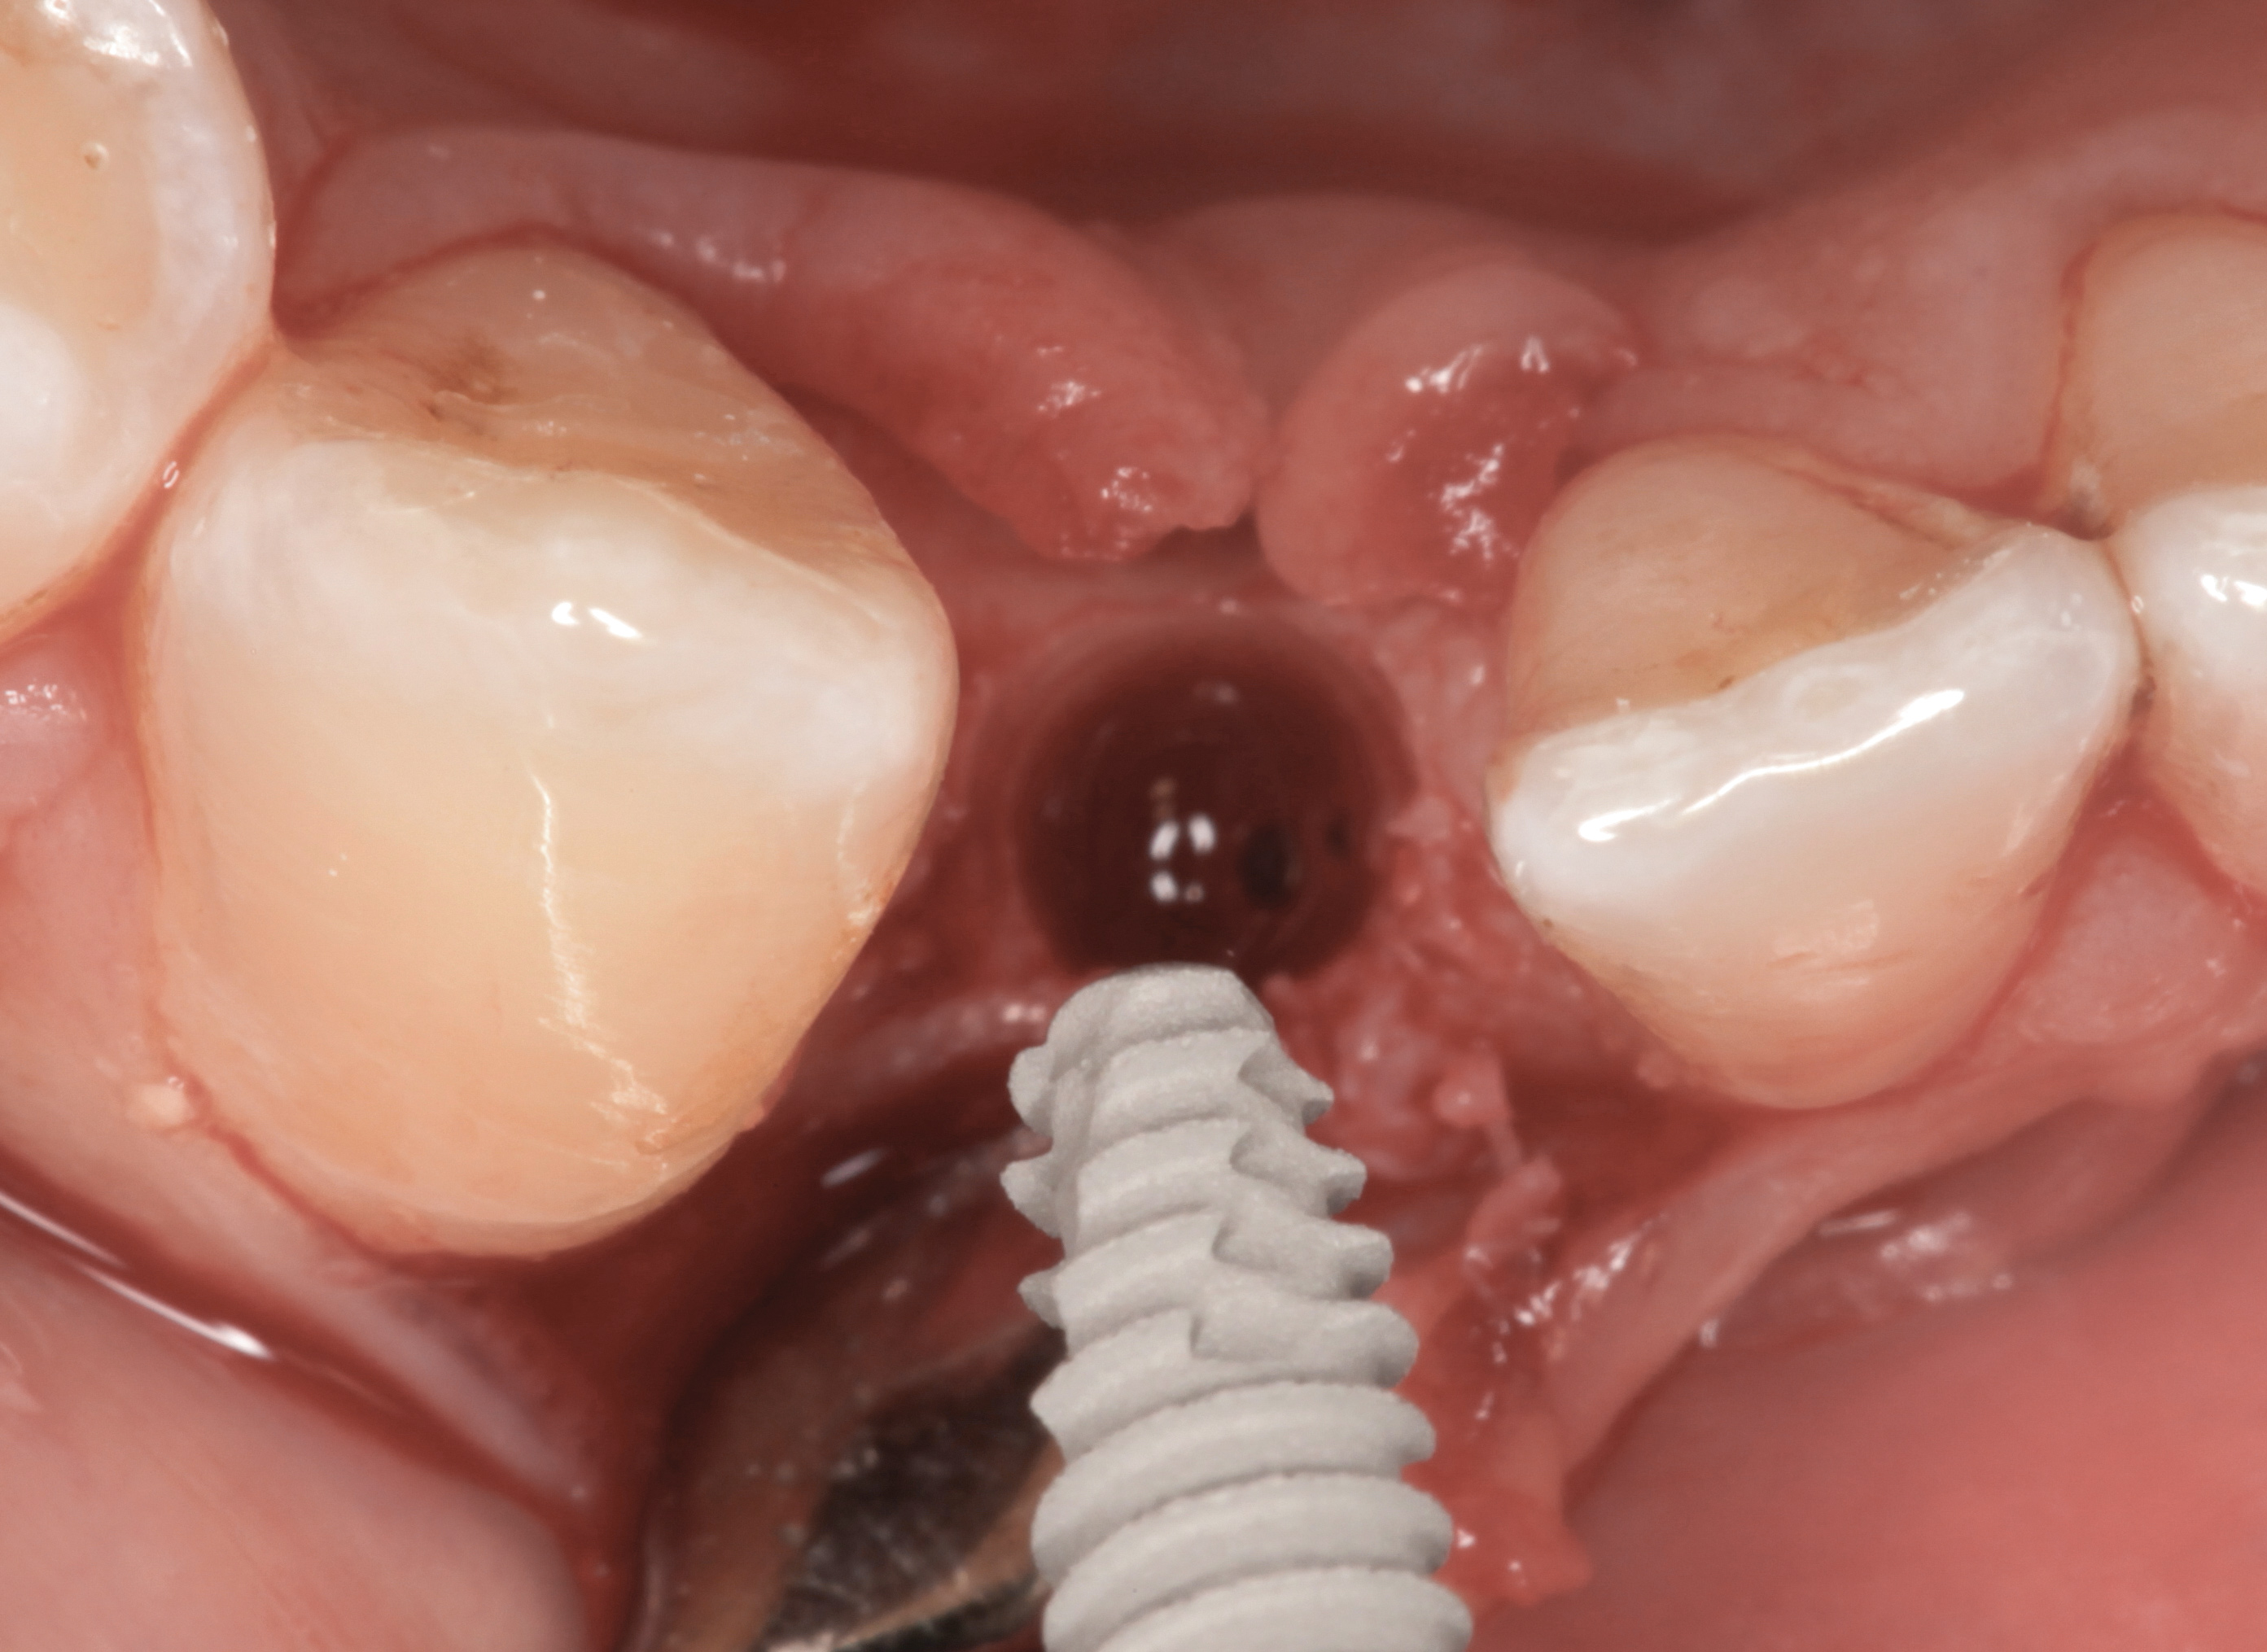

The following case report provides an example of this case scenario: A 24-year-old white male presented with congenitally missing tooth No. 26 restored with a single-tooth cement-retained implant restoration. The implant was placed excessively to the facial aspect of the edentulous site and too shallow, and the periodontal phenotype was thin scalloped (Figure 32). In an effort to mimic the lost midfacial soft tissues, pink ceramics were used as a cosmetic facade. Even though the restoration was not in the esthetic zone, the patient was highly displeased with the esthetic outcome and sought remediation.

The crown and screw-retained custom abutment were removed, and a surgical cover screw was placed into the implant, thereby allowing spontaneous gingival augmentation in situ (Figure 33 and Figure 34). Note that the lingual aspect of the implant site was significantly more coronal than the labial aspect, which was positive because the defect would be limited to a facial–lingual defect. A fixed RBR bridge was cemented on the adjacent teeth and used as a tooth-supported transitional provisional restoration (Figure 35). A few weeks were allotted to let the soft tissue heal and migrate around the cover screw (Figure 36) to see if there would be complete coverage, thereby allowing a soft-tissue augmentation procedure to be performed with primary flap closure as in clinical scenario No. 2. The major obstacle in achieving a positive tissue response was that the implant depth was also deficient because the implant–abutment connection was at the level of the free gingival margin. It was decided that the best treatment option would be to remove the implant. A high-powered reverse-torque device (Fixture Remover Kit, NeoBiotech, www.neobiotechus.com) was used to remove the implant atraumatically (Figure 38 through Figure 41). The implant socket was allowed to heal for several months not unlike an extracted tooth (Figure 42). A new implant was placed in a better position from both a restorative and esthetic perspective (Figure 43), and after a few months of healing, a new crown was made (Figure 44). A satisfactory functional and esthetic result was achieved (Figure 45 and Figure 46) without employing pink porcelain.

Fig 33. Excessive facial angulation of the implant placement shown with an abutment driver in the access screw hole.

Figure 33

Fig 34. A surgical cover screw was placed in an attempt to decoronate the implant and gain soft-tissue coverage in situ.

Figure 34